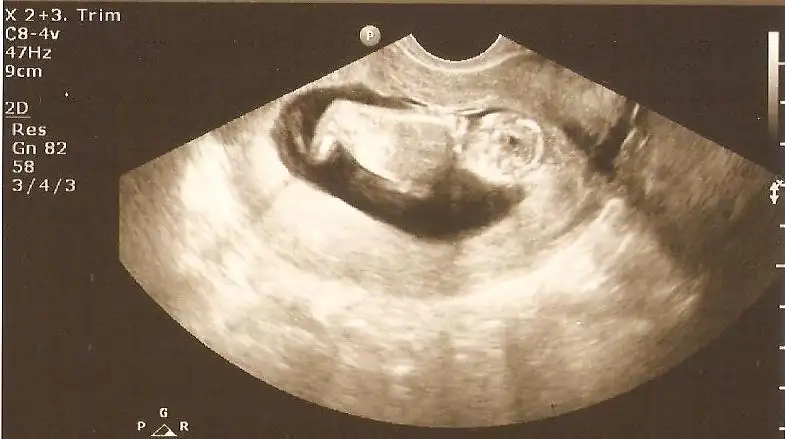

13+3 doktorun fikrini bugün söyledi ama sizde görün istedim bi bakar misiniz

Kızlar yorum lutfennnnnnn lutfen bu yavrunun cinsiyeti ne tahmin yürütün yokmu başka yorum yapannn. Belli olunca yollicam size doktorum 12 haftalık ve 13+ 4 te aynı yorumu yaptı lutfen yorumlarınızı bekliyorum .:((((